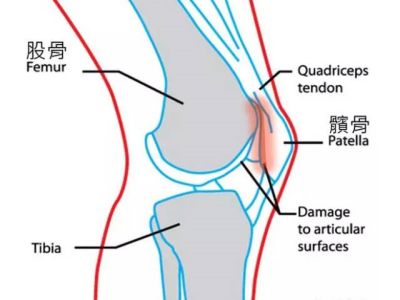

前方疼痛

髌骨软化症

疼痛位置:膝盖前侧

症状:

① 上下楼梯、上下坡时感觉疼痛;

② 蹲下、久坐时感觉不适与疼痛;

③ 膝关节在活动时发出声响。

出现髌骨软化的主要原因除了有一部分人先天髌骨脱位、半脱位外,还和患者运动量过大以及股四头肌力弱,不能有力的保护髌骨处在正常位置上有关。对于髌骨软化症的患者,在缓解期,可以尝试练一练静蹲,对于髌骨软化症有一定的好处。